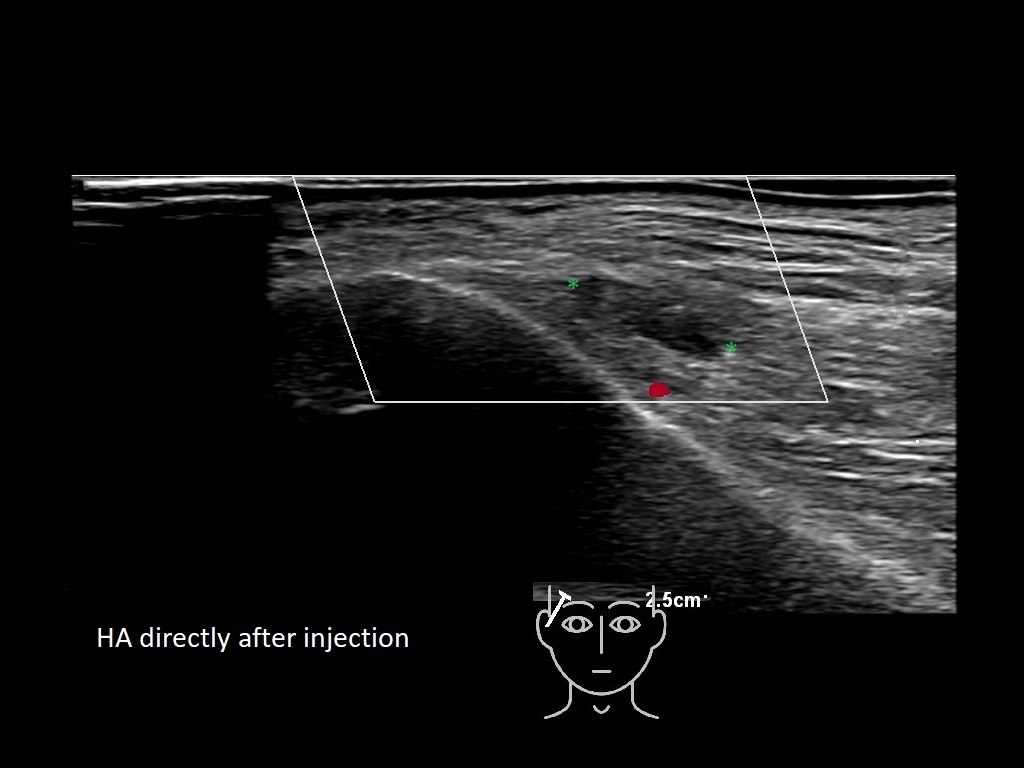

Draw in the second image below where the fillers are located. To check if your answer is correct, swipe the first image to the right.